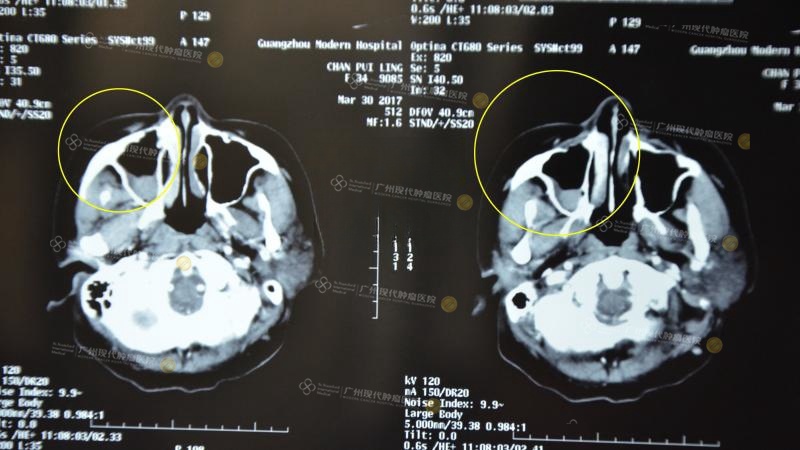

Tháng 3/2017, lần đâu tiên điều trị can thiệp

Dịch ở khoang mũi giảm hẳn, cơ bản đã trở về bình thường, nhãn cầu hồi phục

Trước khi đi điều trị và sau lần can thiệp đầu tiên

“Bà ấy trải qua 4 lần điều trị can thiệp và cấy hạt phóng xạ tại bệnh viện chúng tôi, lần thứ hai điều trị can thiệp, bệnh tình đã chuyển biến tốt hơn. Sau khi trải qua một loạt đièu trị, hiện tại khối u của bà ấy đã hoàn toàn được kiểm soát”. Bác sĩ điều trị chính cho bà Chen đã chia sẻ trong chương trình.

Sau lần thứ tư điều trị can thiệp